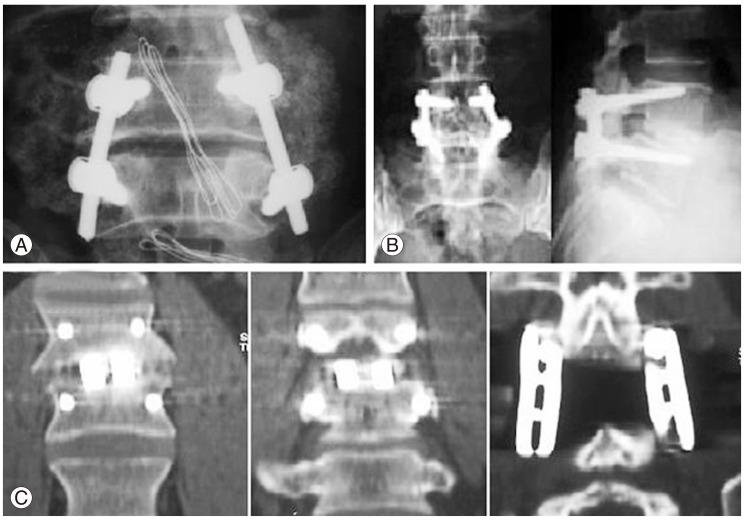

Two hundred patients (88 women, 112 men) were divided into 2 major groups, with 100 patients in group I (implant failure group G1) and 100 patients in group II (successful fusion, control group G2). We subdivided the study groups into two subgroups: subgroup a (single-level instrumented group) and subgroup b (multilevel instrumented group). The implant status was assessed based on intraoperative and follow-up radiographs.

Implant failure in general was present in 36% in G1a, and in 64% in G1b, and types of implant failure included screw fracture (34%), rod fracture (24%), rod loosening (22%), screw loosening (16%), and failure of both rod and screw (4%). Most of the failures (90%) occurred within 6 months after surgery, with no reported cases 1 year postoperatively.